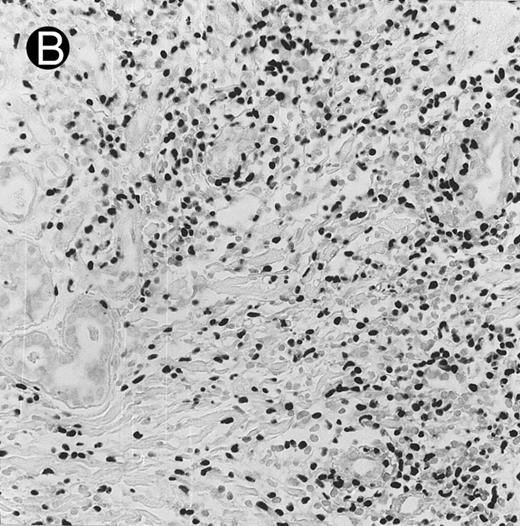

Nasal-type NK/T-cell lymphoma presenting as nodular skin lesion (case no. 28). (A) The skin shows focal necrosis of the epidermis and ulceration (arrow). (B) The lymphoid infiltrate in the dermis shows angiocentricity, as evidenced of the higher density of cells in the expanded walls of the blood vessels (arrows).

Histologically, the lymphomatous infiltrate was diffuse or patchy, with angiocentric and angiodestructive growth being observed in 30 cases (88.2%) (Figs 1 and 2). The cytologic composition was variable from case to case, including predominance of small cells, medium-sized cells, or large cells, or a mixture of these cell types (Fig 2 and 3). The tumor cell nuclei frequently showed irregular foldings and granular chromatin (Fig 2B). The larger cells possessed distinct nucleoli. The cytoplasm was moderate in amount and often pale. Karyorrhexis was usually prominent. Zonal tumor cell death, focal or confluent, was evident in 27 cases. In the 14 cases for which Giemsa-stained touch preparations were available, azurophilic granules could be identified in at least some of the neoplastic cells.